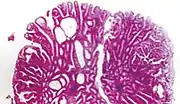

Microvesicular hyperplastic polyp. H&E stain.